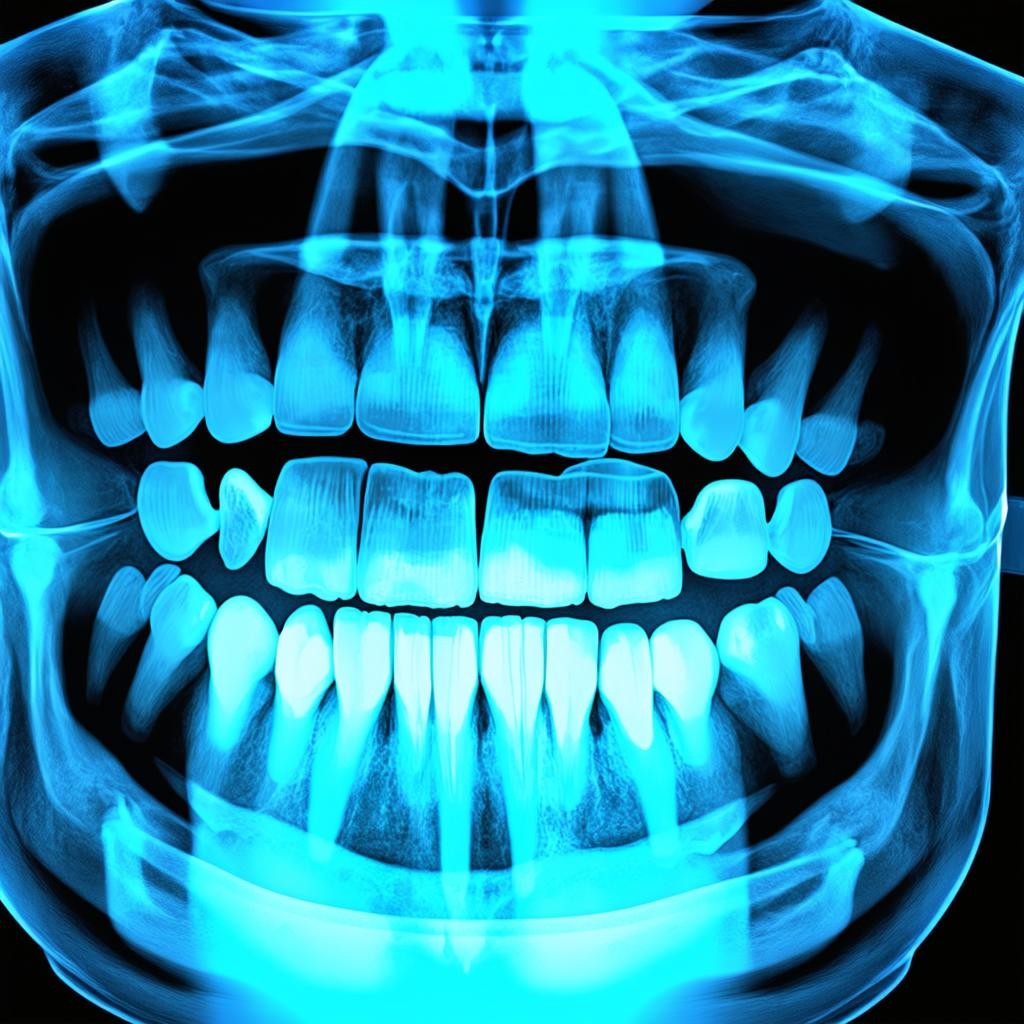

Рентген зубов: современные методы диагностики в стоматологии

Рентгенологическое исследование зубов является неотъемлемой частью современной стоматологической практики. Этот диагностический метод позволяет врачам получить ценную информацию о состоянии зубов и окружающих тканей, которая недоступна при обычном визуальном осмотре. Дентальная рентгенография помогает выявить скрытые патологии, оценить качество проведенного лечения и спланировать дальнейшие терапевтические мероприятия с максимальной точностью.

- Панорамный снимок (ортопантомограмма) - дает общее представление о состоянии всей зубочелюстной системы, включая зубы, челюстные кости и гайморовы пазухи